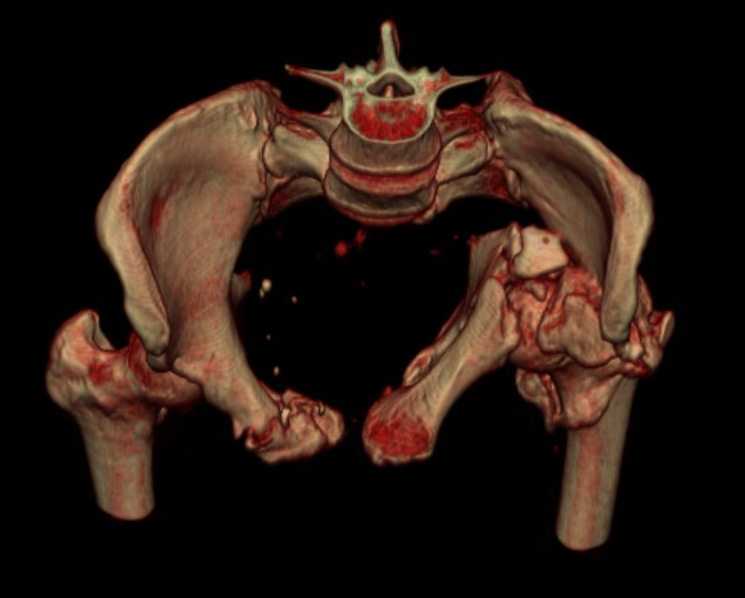

Больная 43 года (промышленный альпинист), 28.07.08 в результате падения с 5 этажа получила политравму: Перелом свода и основания черепа. Вертикально-нестабильное повреждение таза, осложнённое разрывом мочевого пузыря. Чрезвертельный перелом левого бедра. Перелом правой таранной кости, переломовывих правой кубовидной кости. Тупая травма живота, разрыв печени, ушиб почек. Забрюшинная гематома. В день травмы - лапаротомия, ушивание ран печени. Разрыв мочевого пузыря не диагностирован. Течение болезни осложнилось развитием мочевого затёка и обширной пред- и забрюшинной флегмоны, сформировался свищ мочевого пузыря. 19.8.2008 вскрытие, дренировние флегмоны, ревизия мочевого пузыря, обтурация мочевого свища (свищ закрылся в октябре), 1.10.2008 некрэктомия, пластика по Шеде-Лидскому правой кубовидной кости. По результатам КТ диагностирован рак правой почки (диагностическая находка), 8.10.2008 нефрэктомия справа. Переломы велись консервативно. Имеется вертикальное смещение левой половины таза с выраженным отведением крыла (клинически подвижности нет), несросшийся низкий двухколонный перелом левой вертлужной впадины с потерей конгруэнтности, укорочение около5 см, застарелый разрыв лонного сочленения, неправильно сросшиеся переломы обеих ветвей правой лонной кости с укорочением, патологическая подвижность лоно-седалищного фрагмента слева. Правая нижняя конечность неопорна, несмотря на то, что лежа прямую ногу поднимает, ходит на левой ноге (ортопедическая обувь) с костылями, справа тазобедренный ортез. Седалищные нервы работают.Урологи отпустили больную на 6 мес.